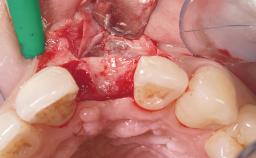

A 33-year-old female patient presented with an upper left central incisor that required extraction after a failed endodontic therapy. The tooth had been traumatized when the patient was a teenager and had undergone several endodontic treatments, including two apicectomy procedures. The patient was in good health and did not smoke. Clinical examination showed that the patient had a high lip line. In full smile, the gingival margins of the upper teeth were visible to the first molars. The gingival margins of central incisors 11 and 21 were only just showing. Examination of tooth 21 confirmed that the tooth was mobile and had hypererupted by 1 mm.

Bone Augmentation Horizontal|Simultaneous

Augmentation Materials Xenogenous|Membrane

Soft Tissue Grafting Simultaneous

Placement Protocol Immediate implant placement